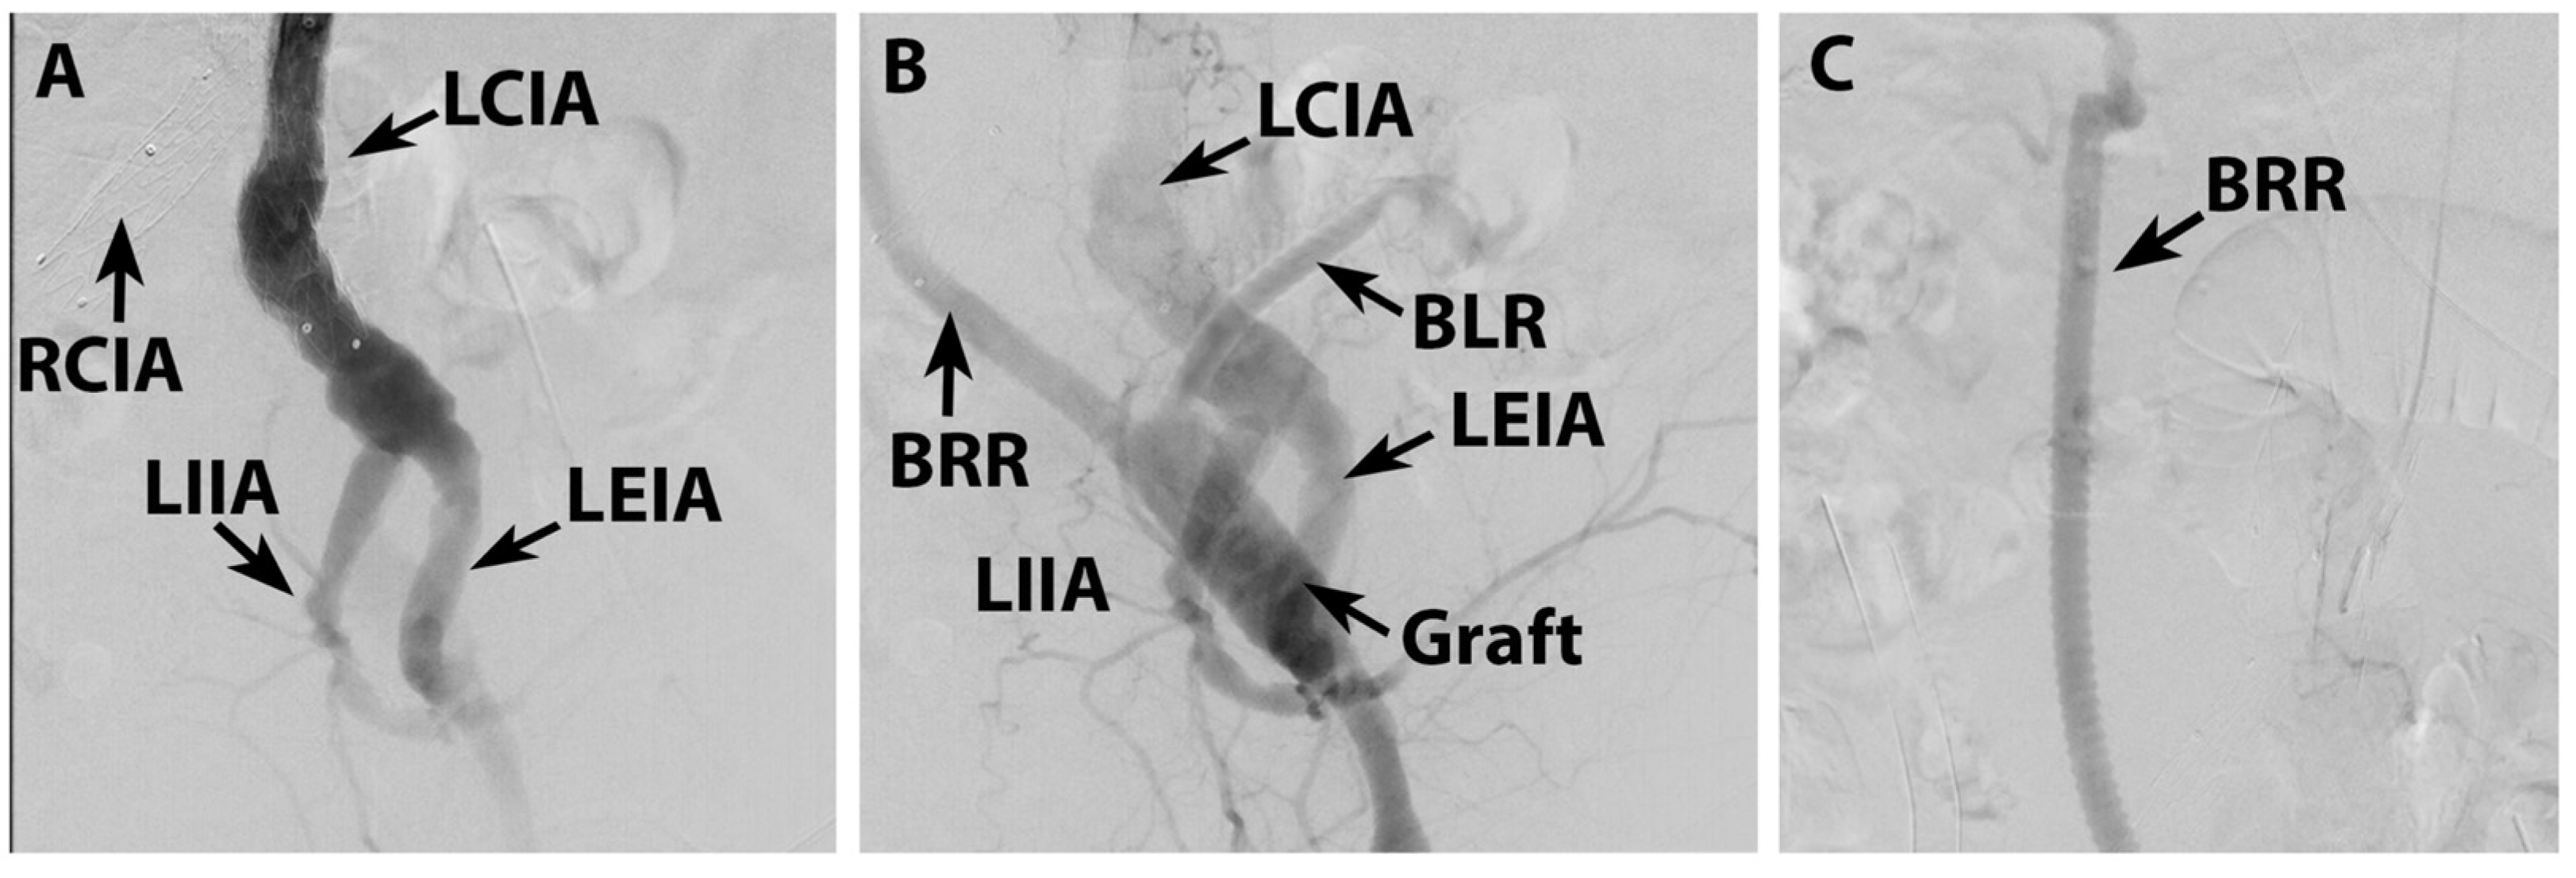

2. Case Report